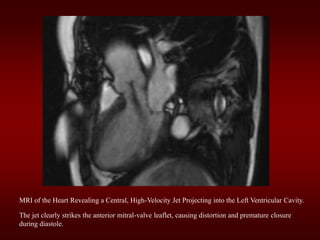

MRI of the Heart Revealing a Central, High-Velocity Jet Projecting into the Left Ventricular Cavity.

The jet clearly strikes the anterior mitral-valve leaflet, causing distortion and premature closure

during diastole.